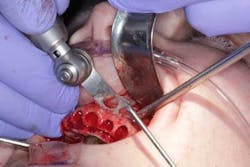

Surgery commenced. Implants on the lower arch were placed first (figures 7 and 8) and then we switched to the maxillary. The teeth were removed (figures 9 and 10) and the ridge was evened out (figures 11-13). The implants were aligned with the denture (figure 14) and then placed accordingly (figures 15-17). Healing caps were put on, and we were ready to start the restorative phase (figures 18-19).